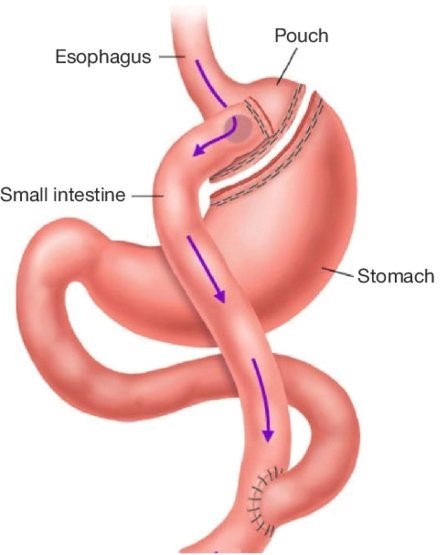

The first cut-free endoscopic treatment for diabesity, ForePass ® is able to replicate the most common types of metabolic surgery (Roux-en-Y Gastric Bypass, RYGB, BilioPancreatic Diversion, and Sleeve Gastrectomy). The first version of our product is aimed at RYGB.

Metabolic Surgery

Only truly effective treatment for diabetes and obesity able to generate 30%+ total body weight loss. Leads to full diabetes, NASH, liver fibrosis, and insulin resistance remission. However, it also leads to 15% complications, including death (0.1-1% with some surgeries).

Designed to replicate metabolic surgery without any cuts to internal organs. As effective on diabetes and obesity as metabolic surgery in animals.

ForePass ® replicates the three most common metabolic surgeries without requiring a single cut

Demonstrated similar efficacy to Gastric Bypass

Conclusion: ForePass ® reduced body weight, glycemia and insulin resistance, and liver fat deposition to the same level of gastric bypass surgery

We demonstrated a full reversal of diabetes and NASH, and weight loss, to levels not statistically different from gastric bypass surgery